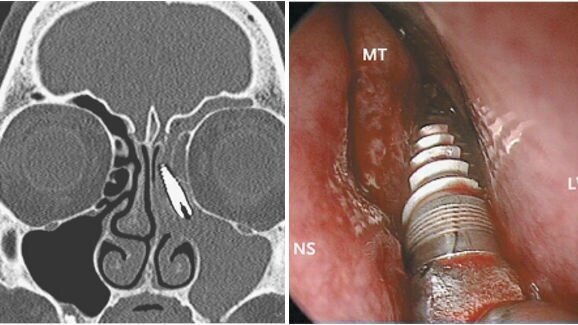

על פי דוח המקרה, שפורסם באינטרנט ב -24 באוקטובר ב-New England Journal of Medicine על ידי חוקרים מאוניברסיטת ברשיה באיטליה, האישה הגיע עקב סינוסיטיס חוזר של הסינוס השמאלי. בדיקת CT חשפה נוכחותו של גוף זר בסינוס האטמואידלי השמאלי שלה.

שנתיים קודם לכן, המטופל עברה טיפול של שתלים בלסת העליונה. עם זאת, בחינה מדוקדקת העלתה כי השתל הדנטלי איננו במקום בו הוא הושתל. הרופאים ביצעו ניתוח אנדוסקופי והוציאו את השתל . המטופלת שוחררה ביום שלאחר ניתוח, תוך שיפור ניכר ומהיר במצבה.

מסקנת החוקרים כי תזוזה של השתל הדנטלי לתוך הסינוס עשויה להיות התוצאה של מיצוב לא תקין של השתל או תוצאה של פריאימפלנטיטיס וספיגת עצם בעקבות כך.